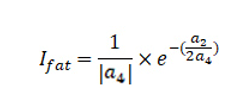

2.2 胖瘦指数定义

通过上述函数图像的特点总结胖瘦指数。

胖瘦指数与四次项系数绝对值成反比,并且与二次项系数和四次项系数的符号关系和绝对值之比有关。胖瘦指数越大,舌体越胖。根据胖瘦特征已知的舌图像样本确定分级标准,可以将舌体描述为“胖”、“不胖不瘦”、“瘦”3种类型。

其中a4为四次项系数,a2为二次项系数。

将得到4次多项式拟合曲线系数代入如下公式,计算胖瘦指数。通过胖瘦指数来判断用户舌体的胖瘦。

其中a4为四次项系数,a2为二次项系数。

胖瘦值数越大说明舌体越宽大,胖瘦指数越小说明舌体越瘦小;胖瘦指数位于4.3-7.8范围内是正常舌,小于4.3是瘦小舌,大于7.8是肥大舌。